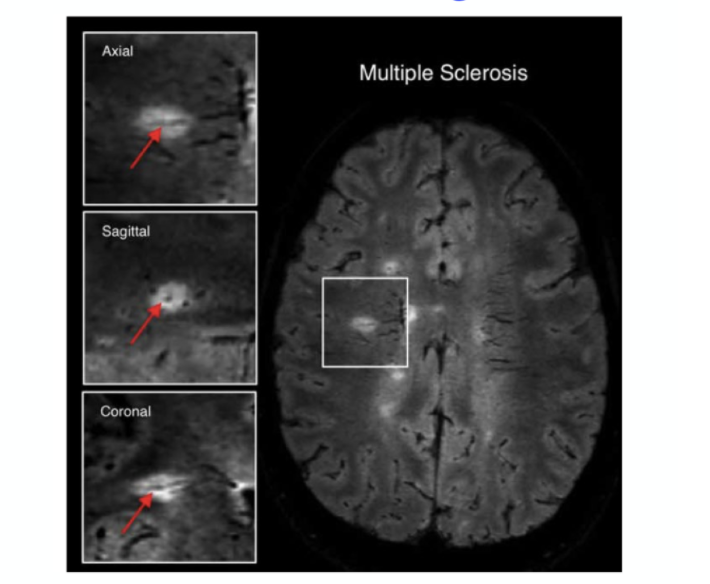

demyelinating plaques appear as ___ lesions on T2 weight MRI.

appear as HYPERDENSE LESIONS on T2 weigth MRI

Characteristics of MS lesions: ovoid, well-circumscribed, oritented perpendicular to lateral ventricles.